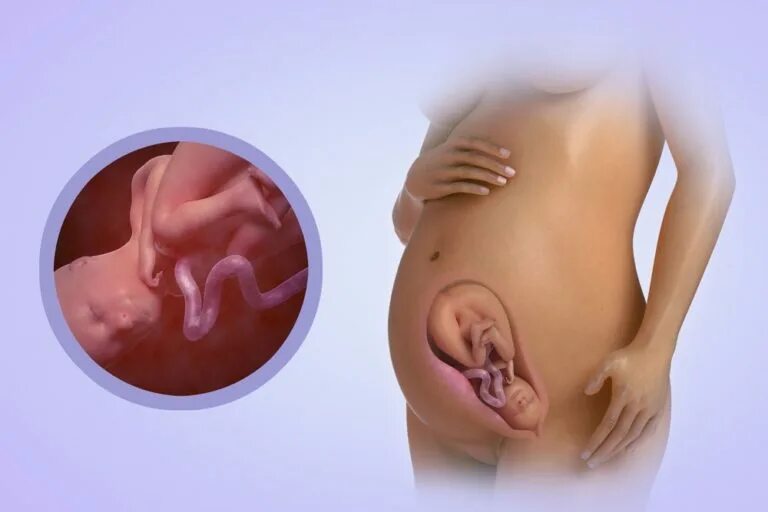

39 недель 2 дня